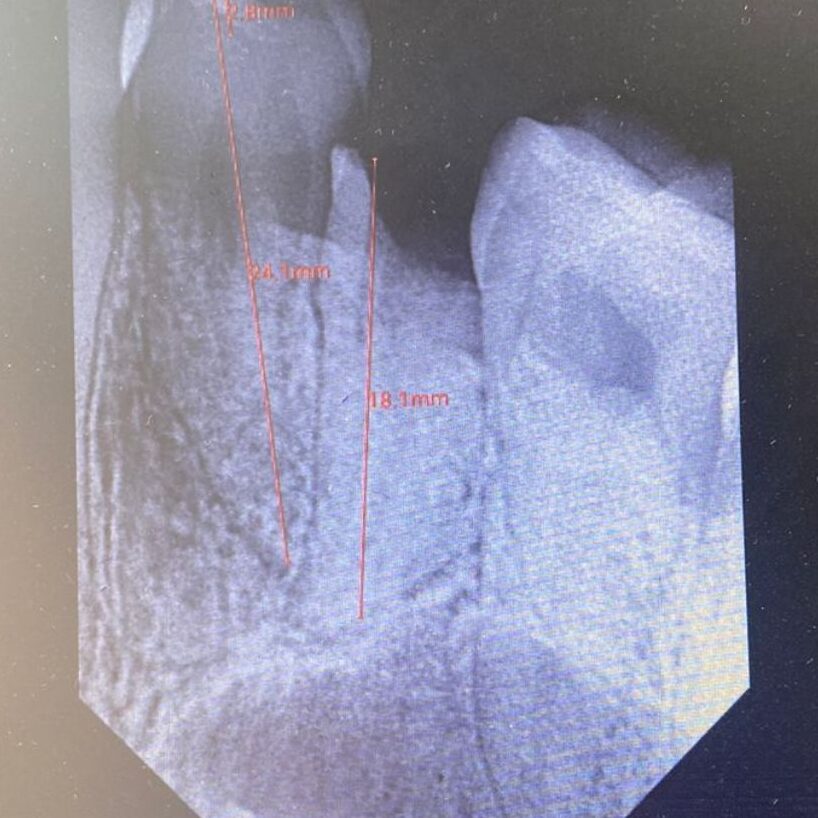

Upon examination, we found that Dr. Ramiz’s upper right second premolar tooth was severely decayed, with only the root remaining. Radiographs confirmed the extent of the damage. Given the tooth’s condition, extraction was the best course of treatment.